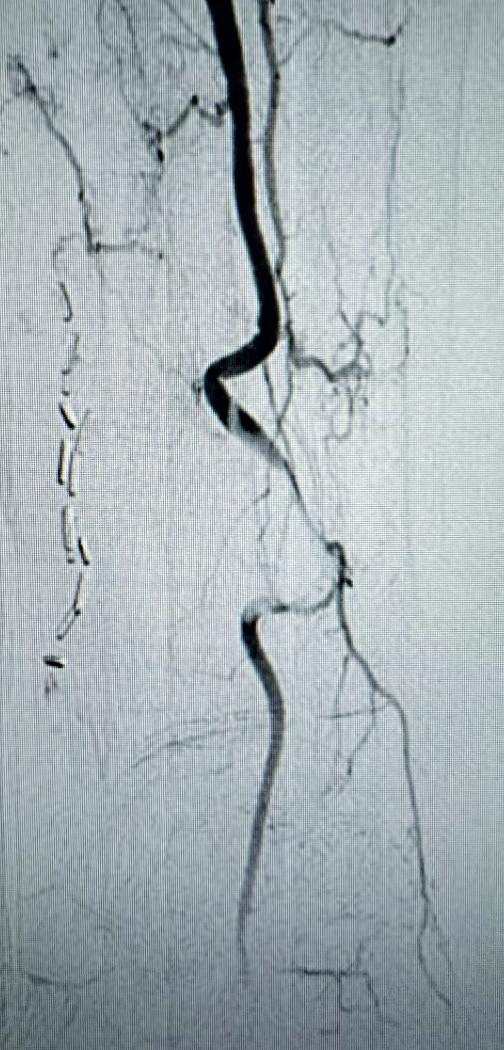

but no intervention was performed. The patient’s son, who lives in the U.S., brought him to the office for vascular surgery evaluation. The patient’s past medical history is notable for hypertension, hypercholesterolemia and a heavy smoking history. On physical examination, he had a palpable left femoral pulse but non-palpable pedal pulses in the left foot. Preoperative ankle brachial index (ABI) of the left lower extremity was severely reduced at 0.31 and the left toe pressure was zero. He was taken to the operating room for a left lower extremity arteriogram and endovascular intervention.

Arteriogram, left lower extremity

An arteriogram of the left lower extremity was performed via antegrade left common femoral artery access based on preoperative review of the lower extremity arteriogram from Uzbekistan. Scattered non-calcified plaque with moderate to high-grade stenoses were identified in the proximal and mid superficial femoral artery. Diffuse severe calcified tibial artery disease was identified. There was a long segment stenosis of the proximal and mid posterior tibial artery coupled with a more distal occlusion. The proximal peroneal artery was calcified and occluded with distal reconstitution identified. There was complete occlusion of the anterior tibial artery (Figure 2).